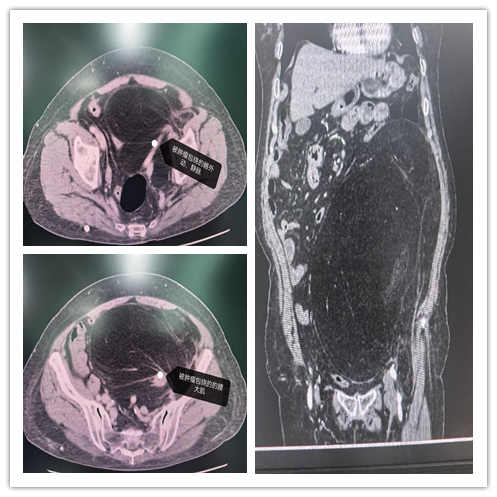

患者为老年女性,因腹胀不适来院就诊。影像学检查提示其腹膜后存在一长径超过40公分的巨大肿瘤,肿瘤已完全包裹左侧腰大肌、髂外动静脉,侵犯髂肌,左侧输尿管显示不清;腹盆腔脏器及腹主动脉明显移位。肿瘤血供丰富,左侧髂内动脉及部分腰动脉参与供血,手术难度极高。